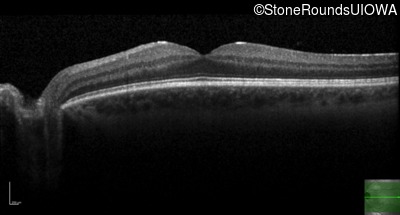

Optical Coherence Tomography - Right - 20/16

Exemplar / OCT Stack

OCT Stack

Optical Coherence Tomography - Left - 20/20 +2